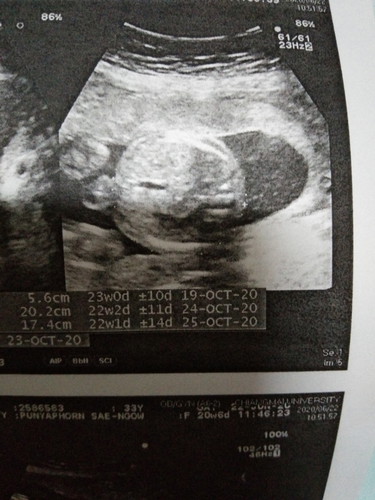

22wk ขอดูภาพอัลตร้าซาวด์แม่ๆหน่อยค่ะ

ล่าสุดค่ะ ตอนนี้ 30w แล้วยังไม่ถึงวันนัด ☺️